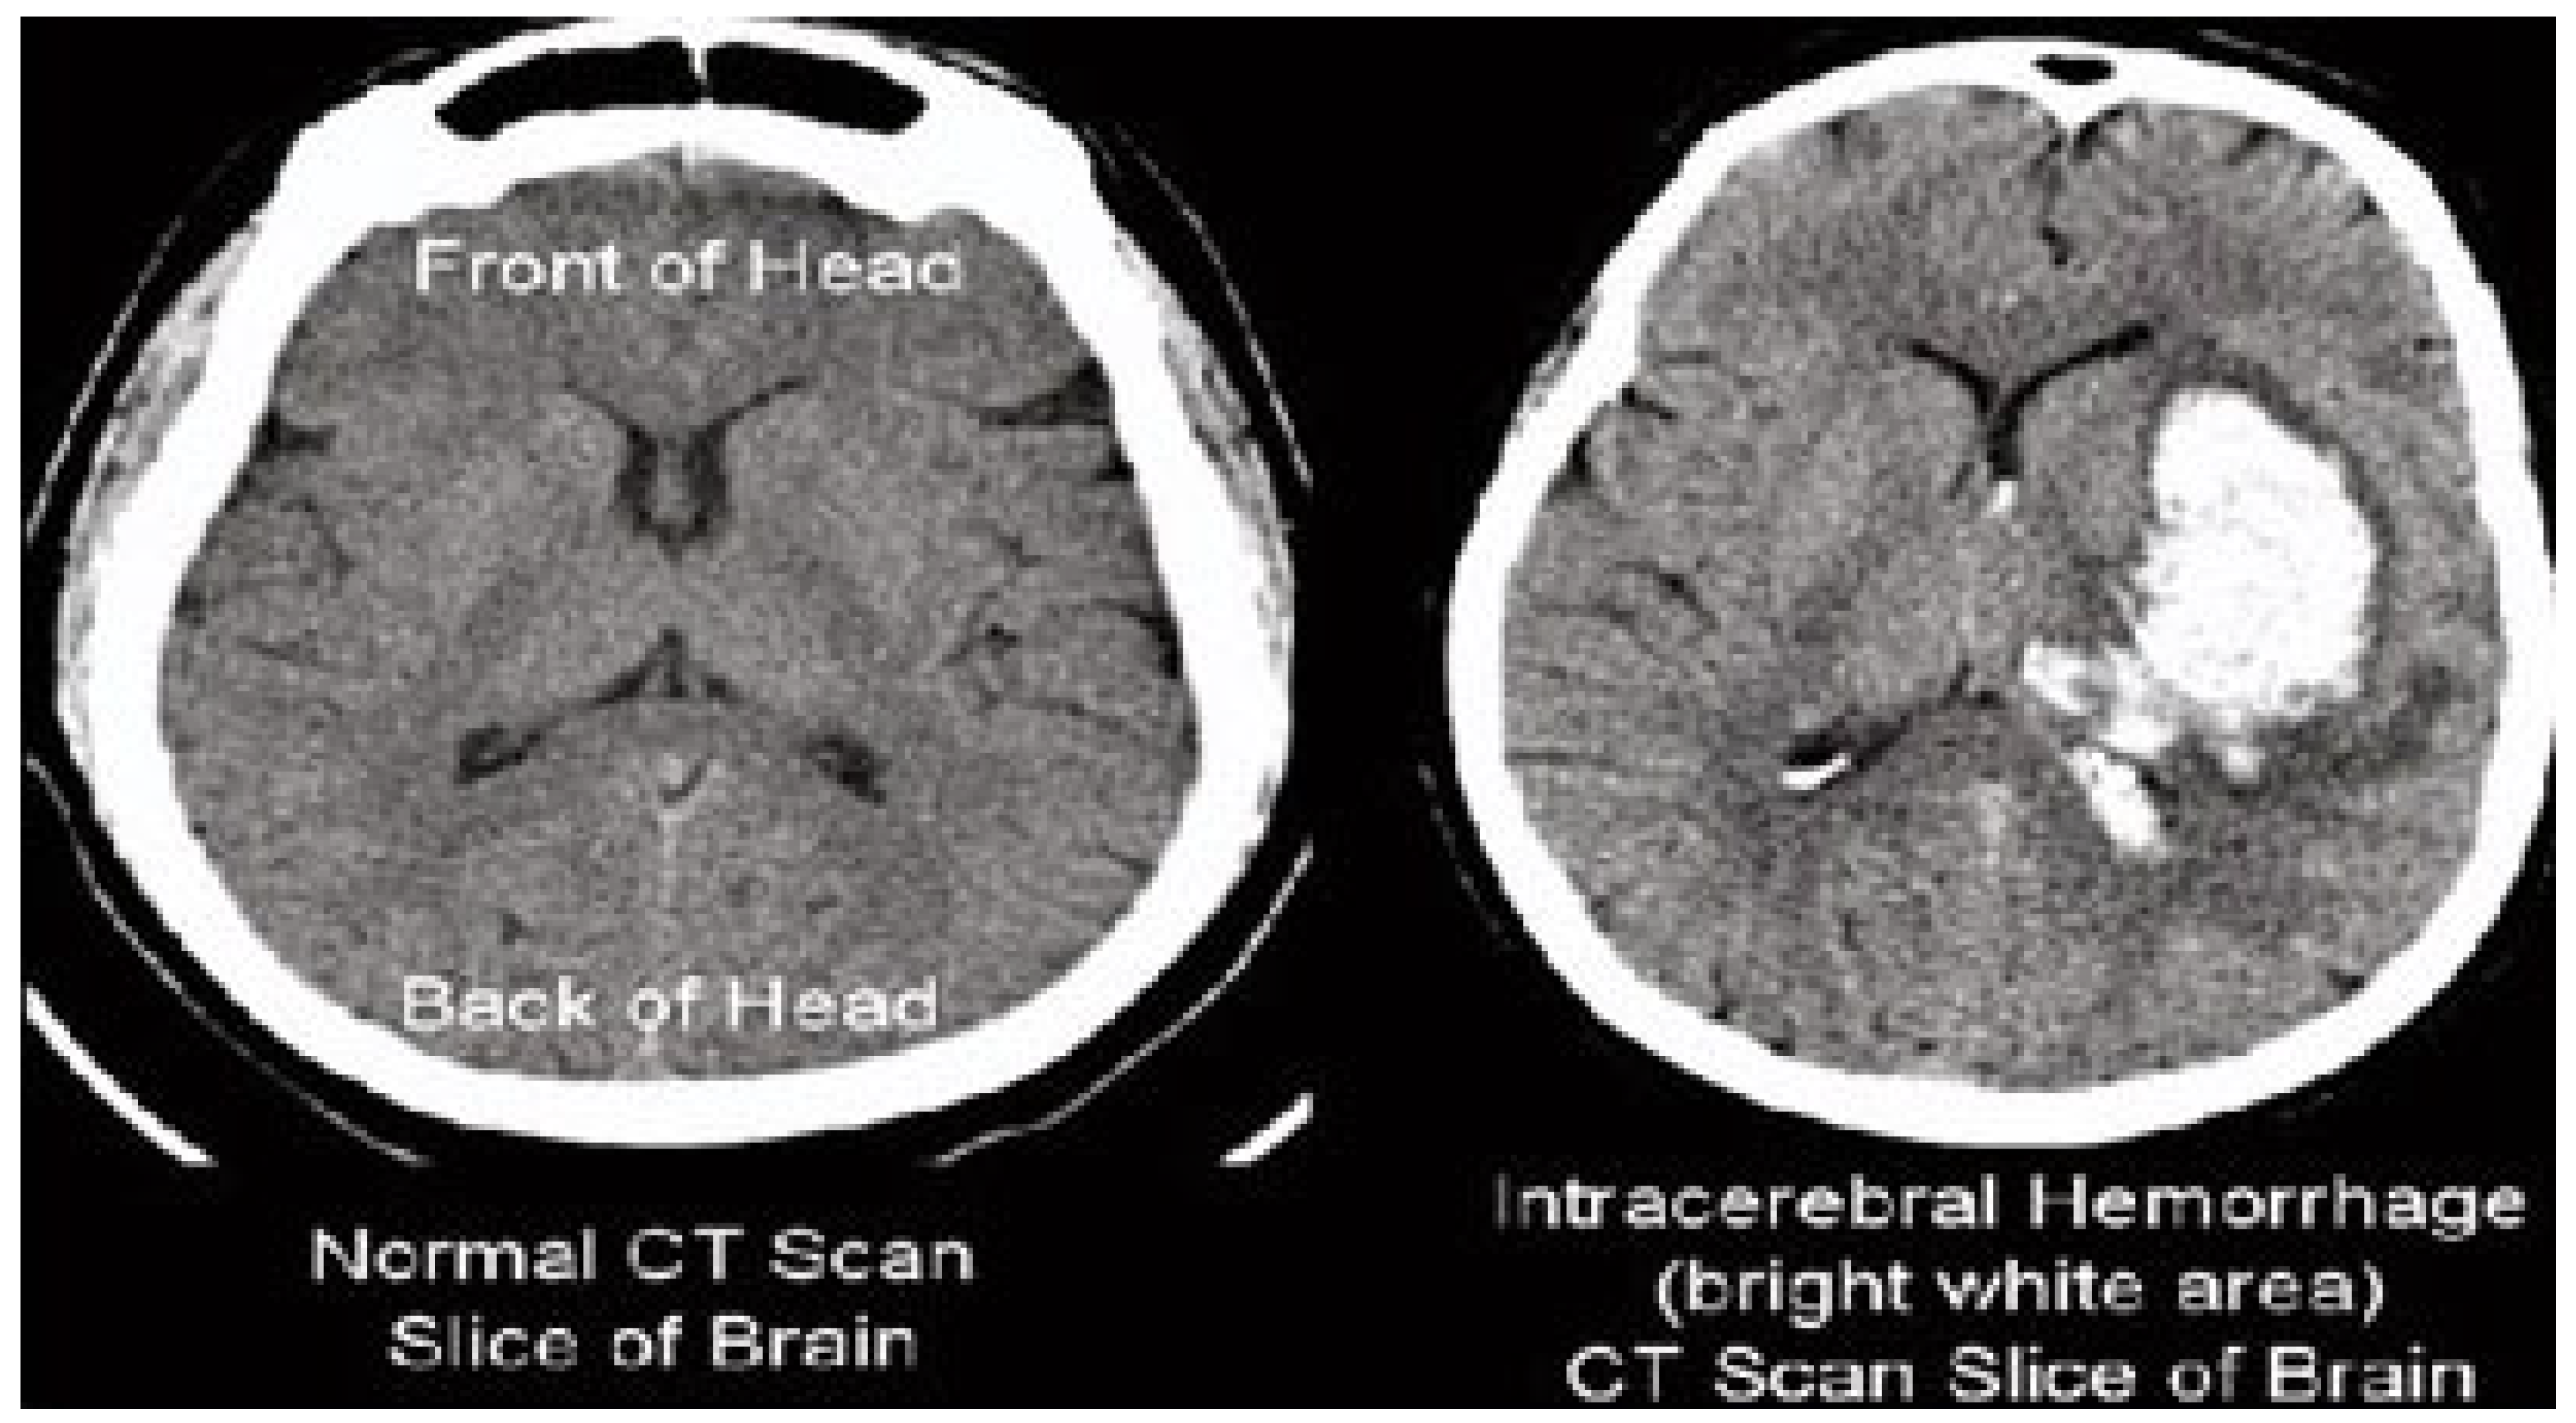

The results of the steganography technique are shown in Figure 2; the changes in both the cover image and the steganography image cannot be distinguished. This demonstrates the superiority of the LSB replacement method in the field of steganography. The resulting steganography image is then transformed to render the image unreadable, and compression techniques are used to store the medical image in a database properly. This scenario is illustrated in Figure 3. This diagram shows the order of conversion, compression, decompression, and inverse conversion processes. To realize this methodology, we took as input cerebral hemorrhage steganography images already embedded in patient data and applied the DWT to obtain the transformed images.

Figure 3.

Hybrid transformation and compression.

The “dwt2” method is used for the conversion. In the DWT process, the original image is decomposed into up to two levels using the “Haar” wavelet. This decomposition produces horizontal, vertical, diagonal, and proximity components. The decomposed components are reconstructed using the DIWT to recover the original image. This strategy is illustrated in Figure 2, and the compression method takes a decomposed image as input and compresses it using a wavelet packet compression technique using “Haar” wavelet packets. The compression method, “wpdencmp,” uses a soft thresholding technique that uses wavelet packets to compress the image and compute the threshold. This compression concept is illustrated in Figure 3, along with histograms of the original and compressed images. A step-by-step compaction process is shown in Figure 4. At each level, the images are refined, and the differences between levels are visible. The higher the number of coding levels of compression, the higher the image’s compression ratio and recovered energy. The compressed image is decompressed by wavelet packet reconstruction using the accounting matrix values of the decomposed image. Horizontal, vertical, diagonal, and proximity components are extracted from the decompressed image, and an IDWT is applied to recover the original image. A title image embedded in the patient data is visualized.

In Figure 3, the steganography image of the brain hemorrhage is taken, and DWT is applied. After compression, the compressed image is displayed as a bar graph. The wavelet reconstruction method recovers the compressed image from the compressed image. The target image is retrieved from the decompressed image by applying the IDWT method to the previous step. Figure 4 represents the DWT and IDWT of the brain hemorrhage image. A sample segmentation of the transformed image is also displayed.

In this research, a picture of a brain hemorrhage was taken and entered into the patient’s records. The input image was transformed using a DWT “branch” wavelet. The transformed image was then compressed using “Haar” wavelet compression. The image was compressed to 83.3333% and decompressed and reconstructed to obtain the embedded brace image. This downloaded brace image was then used to extract patient information from the original image. After decompression, the resolution of the studied image was never disturbed, and since the brace image was lossless, the extracted patient data were unchanged. The optimization obtained from the test significantly contributed to the preservation and long-term archiving of the medical image without compromising the patient’s privacy. The compression technology produced an amazing lossless image after decompression, which was useful for retrieving patient information. The method developed in this research ensured that medical images were archived optimally and increased privacy. JPEG formats’ compression ratio percentages were slightly higher than those of PNG formats. When image size increases, that is, for high-resolution images, the compression ratio lies between 7% and 7.5%, and the compression percentage lies between 30% and 37%. The proposed model increases the expected compression ratio and percentage compared to other models. The average compression ratio lies between 7.8% and 8.6%, and the expected compression ratio lies between 35% and 60%. Computing time is reduced with the proposed method relative to other methods. For high-resolution images, the expected computing time lies between 4 ms and 5 ms.